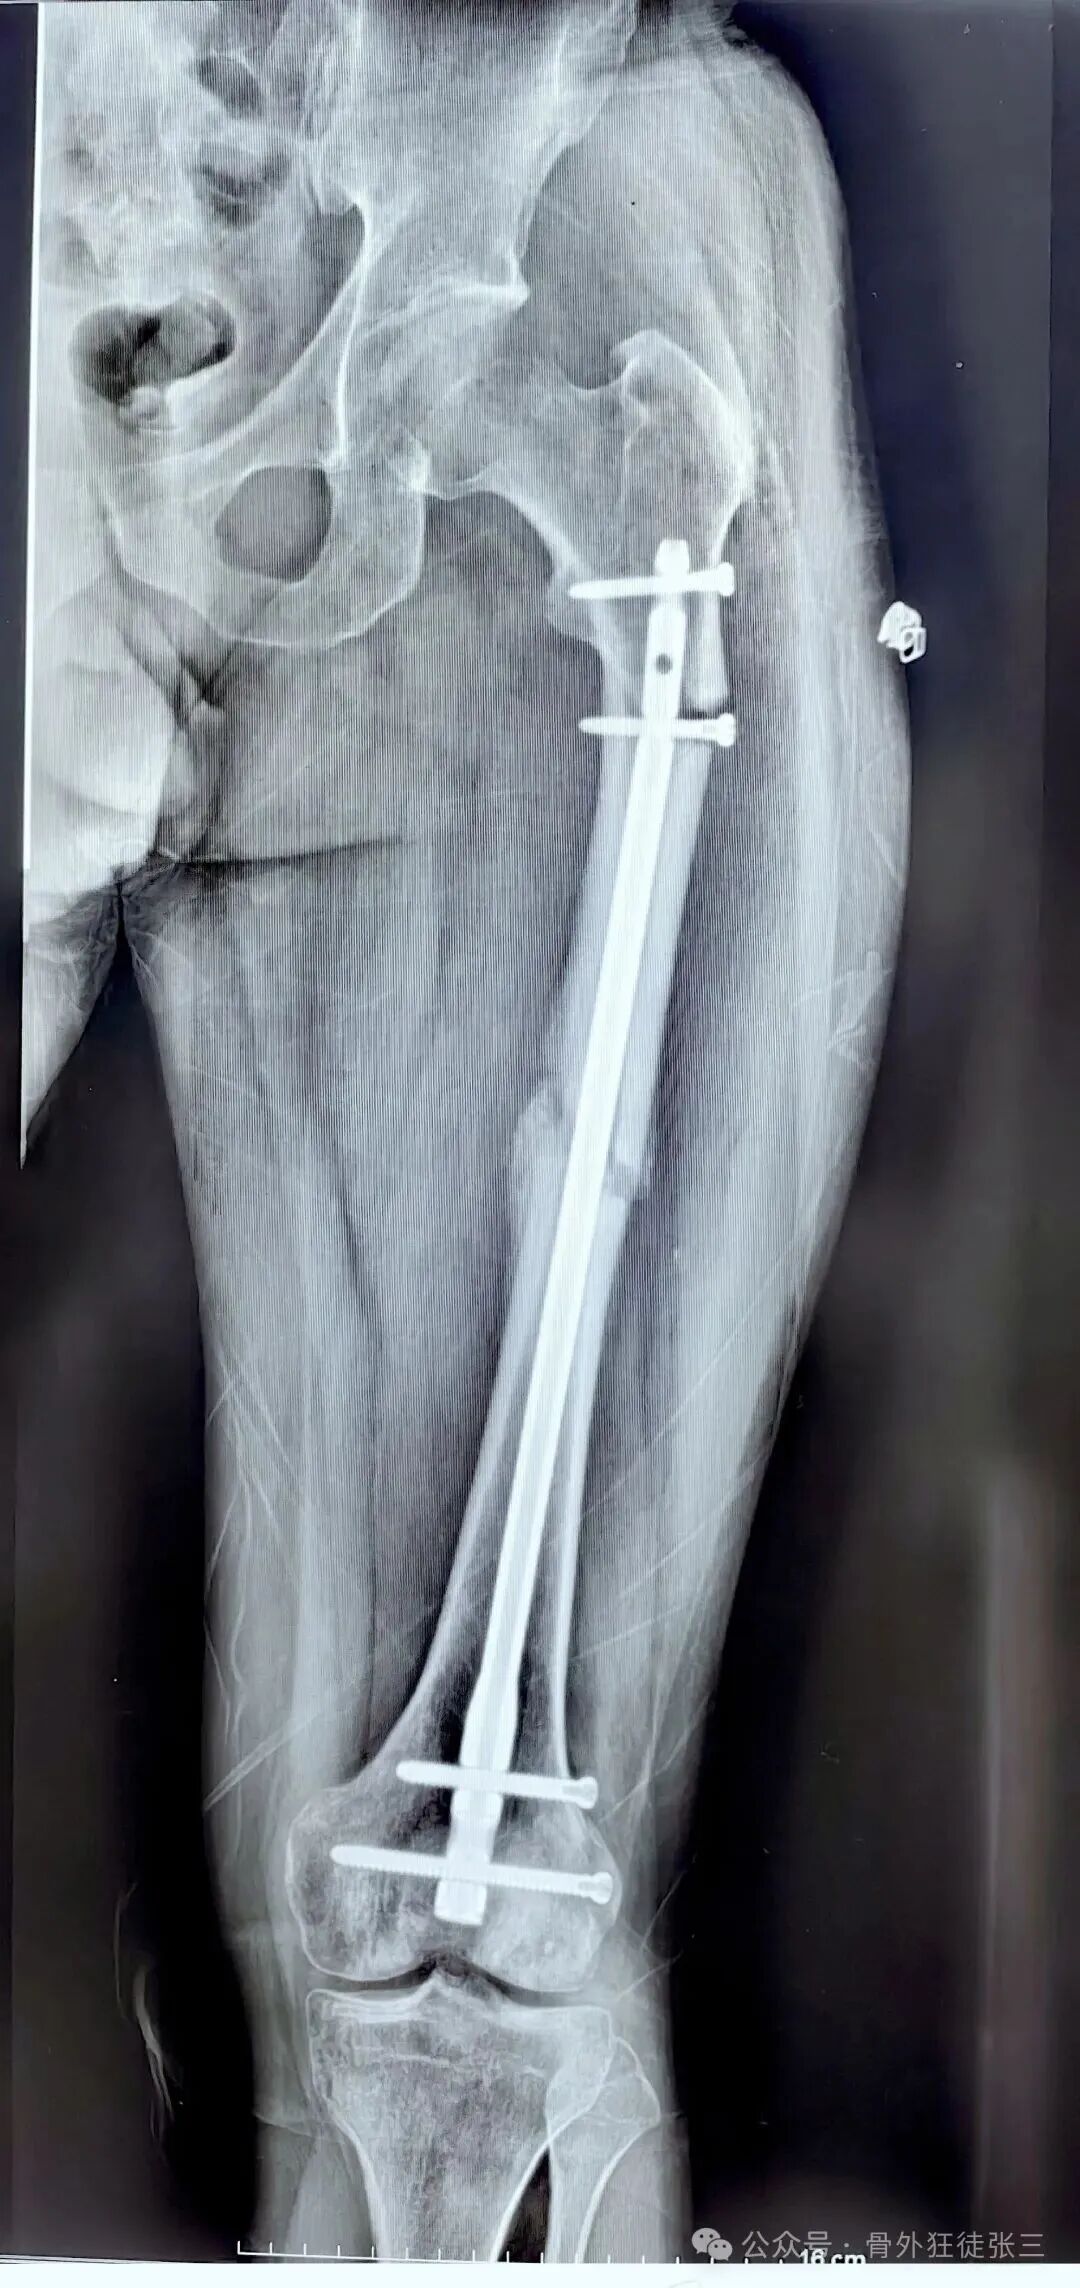

我们给予翻修

1,顺行髓内钉,头颈模式

2,全长保护,

3,最粗,够长

4,扩髓约等于植骨

术后5个月完全愈合

这样全长保护

转子下,股骨颈或者股骨远端再骨折的概率

是不是非常小

几乎不会再出现?